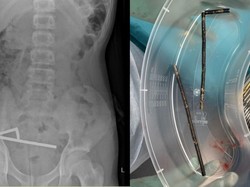

Dokter di Selandia Baru terpaksa mengeluarkan sebagian usus seorang remaja laki-laki berusia 13 tahun. Ini disebabkan adanya 100 magnet yang bersarang di usus.